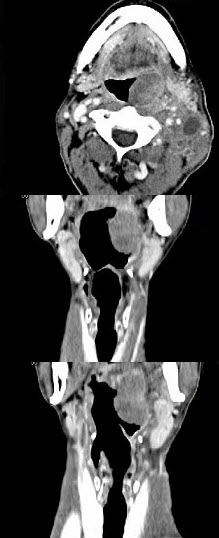

男,67岁,口咽部异物感约8个月,伴口咽部疼痛,患者无明显发热。如图所示最可能的诊断为()。

A、扁桃体结核伴淋巴结转移

B、扁桃体脓肿伴淋巴结转移

C、扁桃体癌伴淋巴结转移

D、扁桃体淋巴瘤

E、下咽癌伴淋巴结转移

C